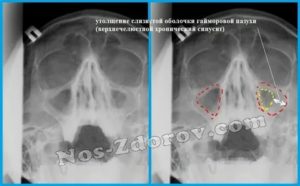

Также при пристеночном гайморите пациента обязательно направляют на рентген. Вот, что позволяет выяснить этот способ:

- Снижение пневматизации верхнечелюстного синуса.

- Состояние орбит глаз и лицевых костей.

- Пристеночное затемнение пазух.

Обычно после проведения рентгена никаких вопросов не остается. Но, если ситуация все еще остается не проясненной, назначают проведение компьютерной томографии. Это очень информативный метод диагностики. Благодаря КТ удается в деталях рассмотреть все структурные изменения пазух, выявить воспаление, уплотнение, деформацию и т. д.

- Пристеночное затемнение на снимке. Его можно заметить на рентгенограмме. Для подтверждения диагноза снимки делают минимум в двух проекциях. Разросшийся эпителий напоминает темные асимметричные пятна. Помимо этого, применяют КТ и МРТ.

Рентген – основной метод диагностики, когда есть подозрение на утолщение слизистой оболочки верхнечелюстных пазух